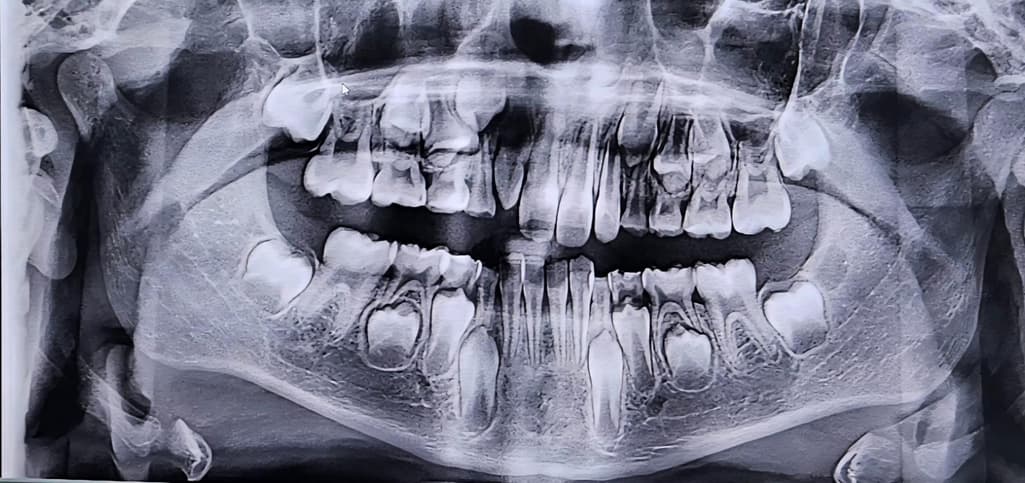

앵글 분류 몇단계 일까요? 대략이라도 부탁드립니다ㅜㅜ

9살아이입니다. 지금은 치료해도 큰 효과를 기대하기 어렵다고 영구치가 다 날때까지 지켜보자 하시는데 보험이 들어있어서 궁금해요ㅜㅜ

앵글분류는 파노라마 상으로는 알수 없고 아직 유치열기라 판단하기가 어렵습니다. 조금더 성장해야 될것같습니다.

교합의 유무를 확인하는 앵글 분류를 확인하기 위해서는 파노라마 사진보다 측면에 새팔로 사진이 필요합니다.

파노라마 사진으로는 교합 유형의 종류를 파악하기 힘듭니다

위 사진으로는 앵글 분류를 알 수는 없습니다. 치과 내원하셔서 검사 해보시는 것이 좋겠습니다.

이 사진만 봐서는 정확히 알기 어렵습니다 셉 사진과 모형채득해서 분석합니다

angle class I 으로 예상됩니다

일반적으로 심한 부정교합, 구순구개 등이 아니면 교정은 보험적용 안됩니다 잘 알아보시기 바랍니다